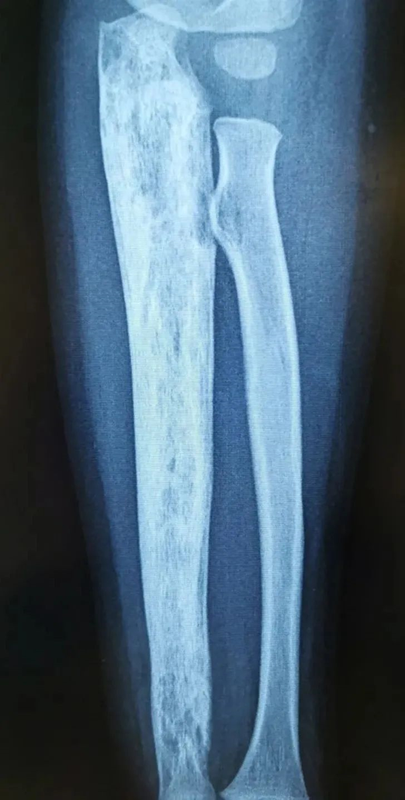

股骨近端骨纖維異樣增殖癥的個體化治療進(jìn)展1、纖維結(jié)構(gòu)不良發(fā)病機(jī)理簡述纖維結(jié)構(gòu)不良(FibrousDysplasia,FD)又稱為骨纖維異樣增殖癥,是一種先天性骨發(fā)育障礙。屬于良性骨樣病損,占所有良性骨腫瘤的7%(JAmAcadOrthopSurg,?2004)。青春期和年輕人多見。由于參與骨代謝的基因(編碼G蛋白亞基)發(fā)生突變,為獲得性功能亢進(jìn)突變,正常體內(nèi)GTP酶活性受到抑制,成骨細(xì)胞內(nèi)cAMP(環(huán)磷酸腺苷)過量產(chǎn)生,正常骨發(fā)育過程障礙,產(chǎn)生了大量異常纖維組織或未成熟的編織骨替代了正常的骨組織(圖1)。此病雖然有基因突變(體細(xì)胞突變),但非遺傳性基因突變(胚胎突變),因此此病不會遺產(chǎn)給下一代。纖維結(jié)構(gòu)不良可為單骨型、多骨型或多骨型合并內(nèi)分泌功能障礙,如合并牛奶咖啡斑和性早熟稱為McCune-Albright綜合征;合并多發(fā)肌內(nèi)粘液瘤,稱為Mazabraud綜合征。圖1:受體G蛋白突變使cAMP(環(huán)磷酸腺苷)過量產(chǎn)生,可刺激垂體、甲狀腺、腎上腺或性腺等;刺激皮膚細(xì)胞產(chǎn)生過量黑色素;出現(xiàn)骨代謝障礙(圖片參考InsightsImaging,2018)。2、纖維結(jié)構(gòu)不良的臨床表現(xiàn)纖維結(jié)構(gòu)不良的臨床表現(xiàn)各種各樣,輕重不一。80%為單骨型,最常見的發(fā)病部位是肋骨、顱骨和股骨;多骨型最常見的部位為顱骨、頜骨、骨盆和股骨。單骨型大多數(shù)患者均為偶然發(fā)現(xiàn),而多骨型在幼年即可被診斷,10歲時出現(xiàn)明顯臨床癥狀,15歲之后不會再出現(xiàn)新的病變部位。單骨型一生中可能不發(fā)展或發(fā)展非常緩慢,但絕不會進(jìn)展為多骨型或Albright綜合征或自行消失。圖2、股骨病變是肢體中最需要外科處理的部位(60%),(圖片參考StrategiesinTraumaandLimbReconstruction,2021)3、纖維結(jié)構(gòu)不良影像學(xué)診斷單骨型和多骨型或合并綜合征的纖維結(jié)構(gòu)不良影像學(xué)表現(xiàn)相同,??蓡螒{X線平片做出診斷。典型的X線表現(xiàn)為膨脹性溶骨性病灶,骨皮質(zhì)變薄,骨皮質(zhì)內(nèi)緣呈扇貝狀,膨脹骨髓腔呈特征性的磨砂玻璃狀。有些小病灶出現(xiàn)較厚的硬化邊。這些征象強烈提示骨纖維結(jié)構(gòu)不良。病變部位沒有正常的骨髓組織和骨基質(zhì),可能出現(xiàn)出血或囊性變,因此纖維結(jié)構(gòu)不良(FD)可繼發(fā)類似于動脈瘤樣骨囊腫(ABC)表現(xiàn)。纖維結(jié)構(gòu)不良病變周圍絕不會出現(xiàn)骨膜反應(yīng)和軟組織腫塊,除非出現(xiàn)了惡性轉(zhuǎn)化,但這種幾率非常罕見。另外,5歲之前一般不建議做骨掃描來除外多骨型,因為在5歲之前的骨掃描不能顯示一些小的病灶,骨掃描正常不能除外多發(fā)性病變。6歲之后所有病變幾乎均可被顯示(InsightsImaging,2018)。沒有癥狀和骨折的患者,2年復(fù)查一次。肢體其他部位的病變不必要每次都進(jìn)行X線片檢查,但對于股骨的病變的患者要求每次復(fù)查X線片,觀察畸形的變化。FD病變可被描述為靜止(穩(wěn)定)、活躍(緩慢生長)和侵襲(生長迅速,并出現(xiàn)疼痛、病理性骨折、神經(jīng)壓迫或惡性轉(zhuǎn)化表現(xiàn))。圖3、靜止性病變。男性40歲(A),女性55歲(B)女性75歲(C)。三名患者均為偶然發(fā)現(xiàn)股骨頸“磨砂玻璃樣”病變,邊緣硬化,無皮質(zhì)破壞,邊界清楚,為典型纖維結(jié)構(gòu)不良表現(xiàn),不需要手術(shù),定期復(fù)查無變化。圖4、活躍或侵襲性病變。女性18歲(A),男性27歲(B),男性14歲(C),女性29歲(D),女性23歲(E),女性30歲,“牧羊拐”(F)。這些都有病理性骨折的風(fēng)險或已存在病理性骨折,需要手術(shù)治療4、為啥需要特別關(guān)注股骨近端纖維結(jié)構(gòu)不良由上可見,無論單骨型還是多骨型,股骨都是臨床上最常見的受累部位。尤其在股骨近端,承受了身體的垂直壓力和旋轉(zhuǎn)應(yīng)力,此部位的骨強度減弱,很容易出現(xiàn)疼痛和病理性骨折,大部分需要外科手段干預(yù)。如下圖,股骨近端出現(xiàn)病理性骨折的比例高達(dá)40%(圖5)。股骨近端病理性骨折或“牧羊拐”畸形矯形在臨床上極具挑戰(zhàn)性!至今沒有確切的關(guān)于股骨近端矯形的臨床指南,報道的病例也是依賴不同大夫的經(jīng)驗,根據(jù)每個患者的具體情況進(jìn)行個體化處理。圖5、股骨近端纖維結(jié)構(gòu)不良(圖片參考JChildOrthop,2014)5、個體化治療股骨近端靜止性病變不建議刮除植骨治療,觀察即可;活躍性病變主要位于股骨頸,股骨粗隆外側(cè)皮質(zhì)正?;颊撸墒褂梦?chuàng)空心釘內(nèi)固定;出現(xiàn)股骨近端病理性骨折的患者,建議DHS動力髖螺釘、股骨近端鋼板或近段髓內(nèi)針治療,如果同時存在股骨弓狀畸形,可同時截骨矯正股骨畸形或待骨折愈合后二期再處理;對于股骨近端“牧羊拐”截骨矯形后使用股骨全長髓內(nèi)針恢復(fù)下肢力線是相對比較公認(rèn)的內(nèi)固定手段。纖維結(jié)構(gòu)不良的治療既往認(rèn)為需要處理病灶、植骨,但現(xiàn)在認(rèn)為應(yīng)該以預(yù)防和避免病理性骨折,或畸形矯正為主要目的。遵循矯形原則,恢復(fù)下肢力線和活動功能,F(xiàn)D截骨矯形后骨愈合能力沒有問題(JBoneJointSurgAm,?1998;JChildOrthop,2014;OrphanetJournalofRareDiseases,2018;StrategiesinTraumaandLimbReconstruction,2021)。6、兒童患者的治療難點兒童患者的特點是股骨頭骨骺和大粗隆骨骺沒有閉合,且股骨髓腔較細(xì),股骨近端直徑小,常規(guī)成人髓內(nèi)針和DHS動力髖螺釘、股骨近端解剖板可能損傷骨骺或無法使用。矯形后隨著年齡增長,畸形容易復(fù)發(fā),且某些多骨型患者股骨近端、股骨頸和股骨頭可能都受累,內(nèi)固定不牢固,容易失敗。出現(xiàn)股骨近端病理性骨折的患者,可以使用成人肱骨髓內(nèi)針或肱骨近端解剖鋼板替代,但需要與家屬充分溝通,手術(shù)只是穩(wěn)定骨折,對疾病發(fā)展沒有實質(zhì)性作用。對于無癥狀無病理性骨折兒童患者是否需要過于積極的進(jìn)行早期處理和畸形矯正沒有定論。7、藥物治療進(jìn)展纖維結(jié)構(gòu)不良的溶骨性破壞有破骨細(xì)胞參與,RANKL通路活躍,臨床上既往應(yīng)用二膦酸鹽制劑,如唑來膦酸等輔助治療纖維結(jié)構(gòu)不良,近來逐漸被地舒單抗替代,原因在于地舒單抗臨床使用方便,且在回顧性多中心研究中顯示對于唑來膦酸無效的患者,使用地舒單抗仍然有效(Bone,2023)。雖然目前地舒單抗在臨床上應(yīng)用于纖維結(jié)構(gòu)不良為超適應(yīng)證用藥,但在纖維結(jié)構(gòu)不良患者上應(yīng)用是安全有效的(NEnglJMed,2023)。對于纖維結(jié)構(gòu)不良患者使用地舒單抗,需要應(yīng)用前告知患者。8、典型病例1)女性,30歲,右股骨近端病理性骨折,微創(chuàng)空心釘內(nèi)固定,人工骨注射。術(shù)后1個月活動錄像2)男性31歲,因疼痛發(fā)現(xiàn)左股骨近端纖維異樣增殖癥,病理性骨折。手術(shù)采用病灶刮除,自體腓骨和異體骨植入,鋼板內(nèi)固定術(shù)。術(shù)后2.5年復(fù)查,骨折愈合良好,無復(fù)發(fā),患者日?;顒雍瓦\動完全正常(錄像)3)、男性,28歲,疼痛發(fā)現(xiàn)右股骨近端纖維異樣增殖癥,骨折風(fēng)險很高,建議手術(shù),然而在等待住院期間行走時突然摔倒,出現(xiàn)病理性骨折,急診手術(shù)4)、男性,43歲,年輕時在當(dāng)?shù)匦杏夜晒腔纬C正鋼板內(nèi)固定,但矯正不滿意?,F(xiàn)股骨近端出現(xiàn)病理性骨折。這個病人首先處理病理性骨折,將原固定鋼板取出,股骨近段髓內(nèi)針骨折內(nèi)固定,待二期再進(jìn)行股骨畸形矯正5)、男性,29歲,左股骨近端“牧羊拐”畸形,兒時曾行股骨彈性針置入,隨著年齡增長,畸形仍持續(xù)加重,現(xiàn)雙下肢相差7cm,患者行走跛行重,患者體重也較大,活動后容易疲勞不適,影響正常生活。制定詳細(xì)手術(shù)計劃,我們使用最新的3D打印技術(shù),術(shù)前計算機(jī)模擬截骨角度,髓內(nèi)針植入長度和位置,矯形后效果等。術(shù)中通過3D截骨導(dǎo)板,精確截骨矯形,髓內(nèi)針內(nèi)固定。患者矯形后雙下肢基本等長,隨訪骨折愈合良好。術(shù)后三個月復(fù)查,建議逐漸脫拐(活動錄像)9、總結(jié)股骨近端纖維結(jié)構(gòu)不良容易出現(xiàn)病理性骨折或合并“牧羊拐”畸形,其臨床治療充滿挑戰(zhàn),包括手術(shù)內(nèi)固定的選擇、骨質(zhì)條件差、是否一期進(jìn)行矯形、矯形可能需要進(jìn)行多次手術(shù)以及兒童股骨近端纖維結(jié)構(gòu)不良的治療等。目前沒有現(xiàn)成的指南應(yīng)用,強調(diào)個體化治療。隨著3D打印技術(shù)的出現(xiàn),術(shù)前制定詳細(xì)的手術(shù)計劃,術(shù)中精確截骨矯形是最大進(jìn)展,為手術(shù)帶來了便利,患者也獲得了良好的手術(shù)收益-風(fēng)險比。